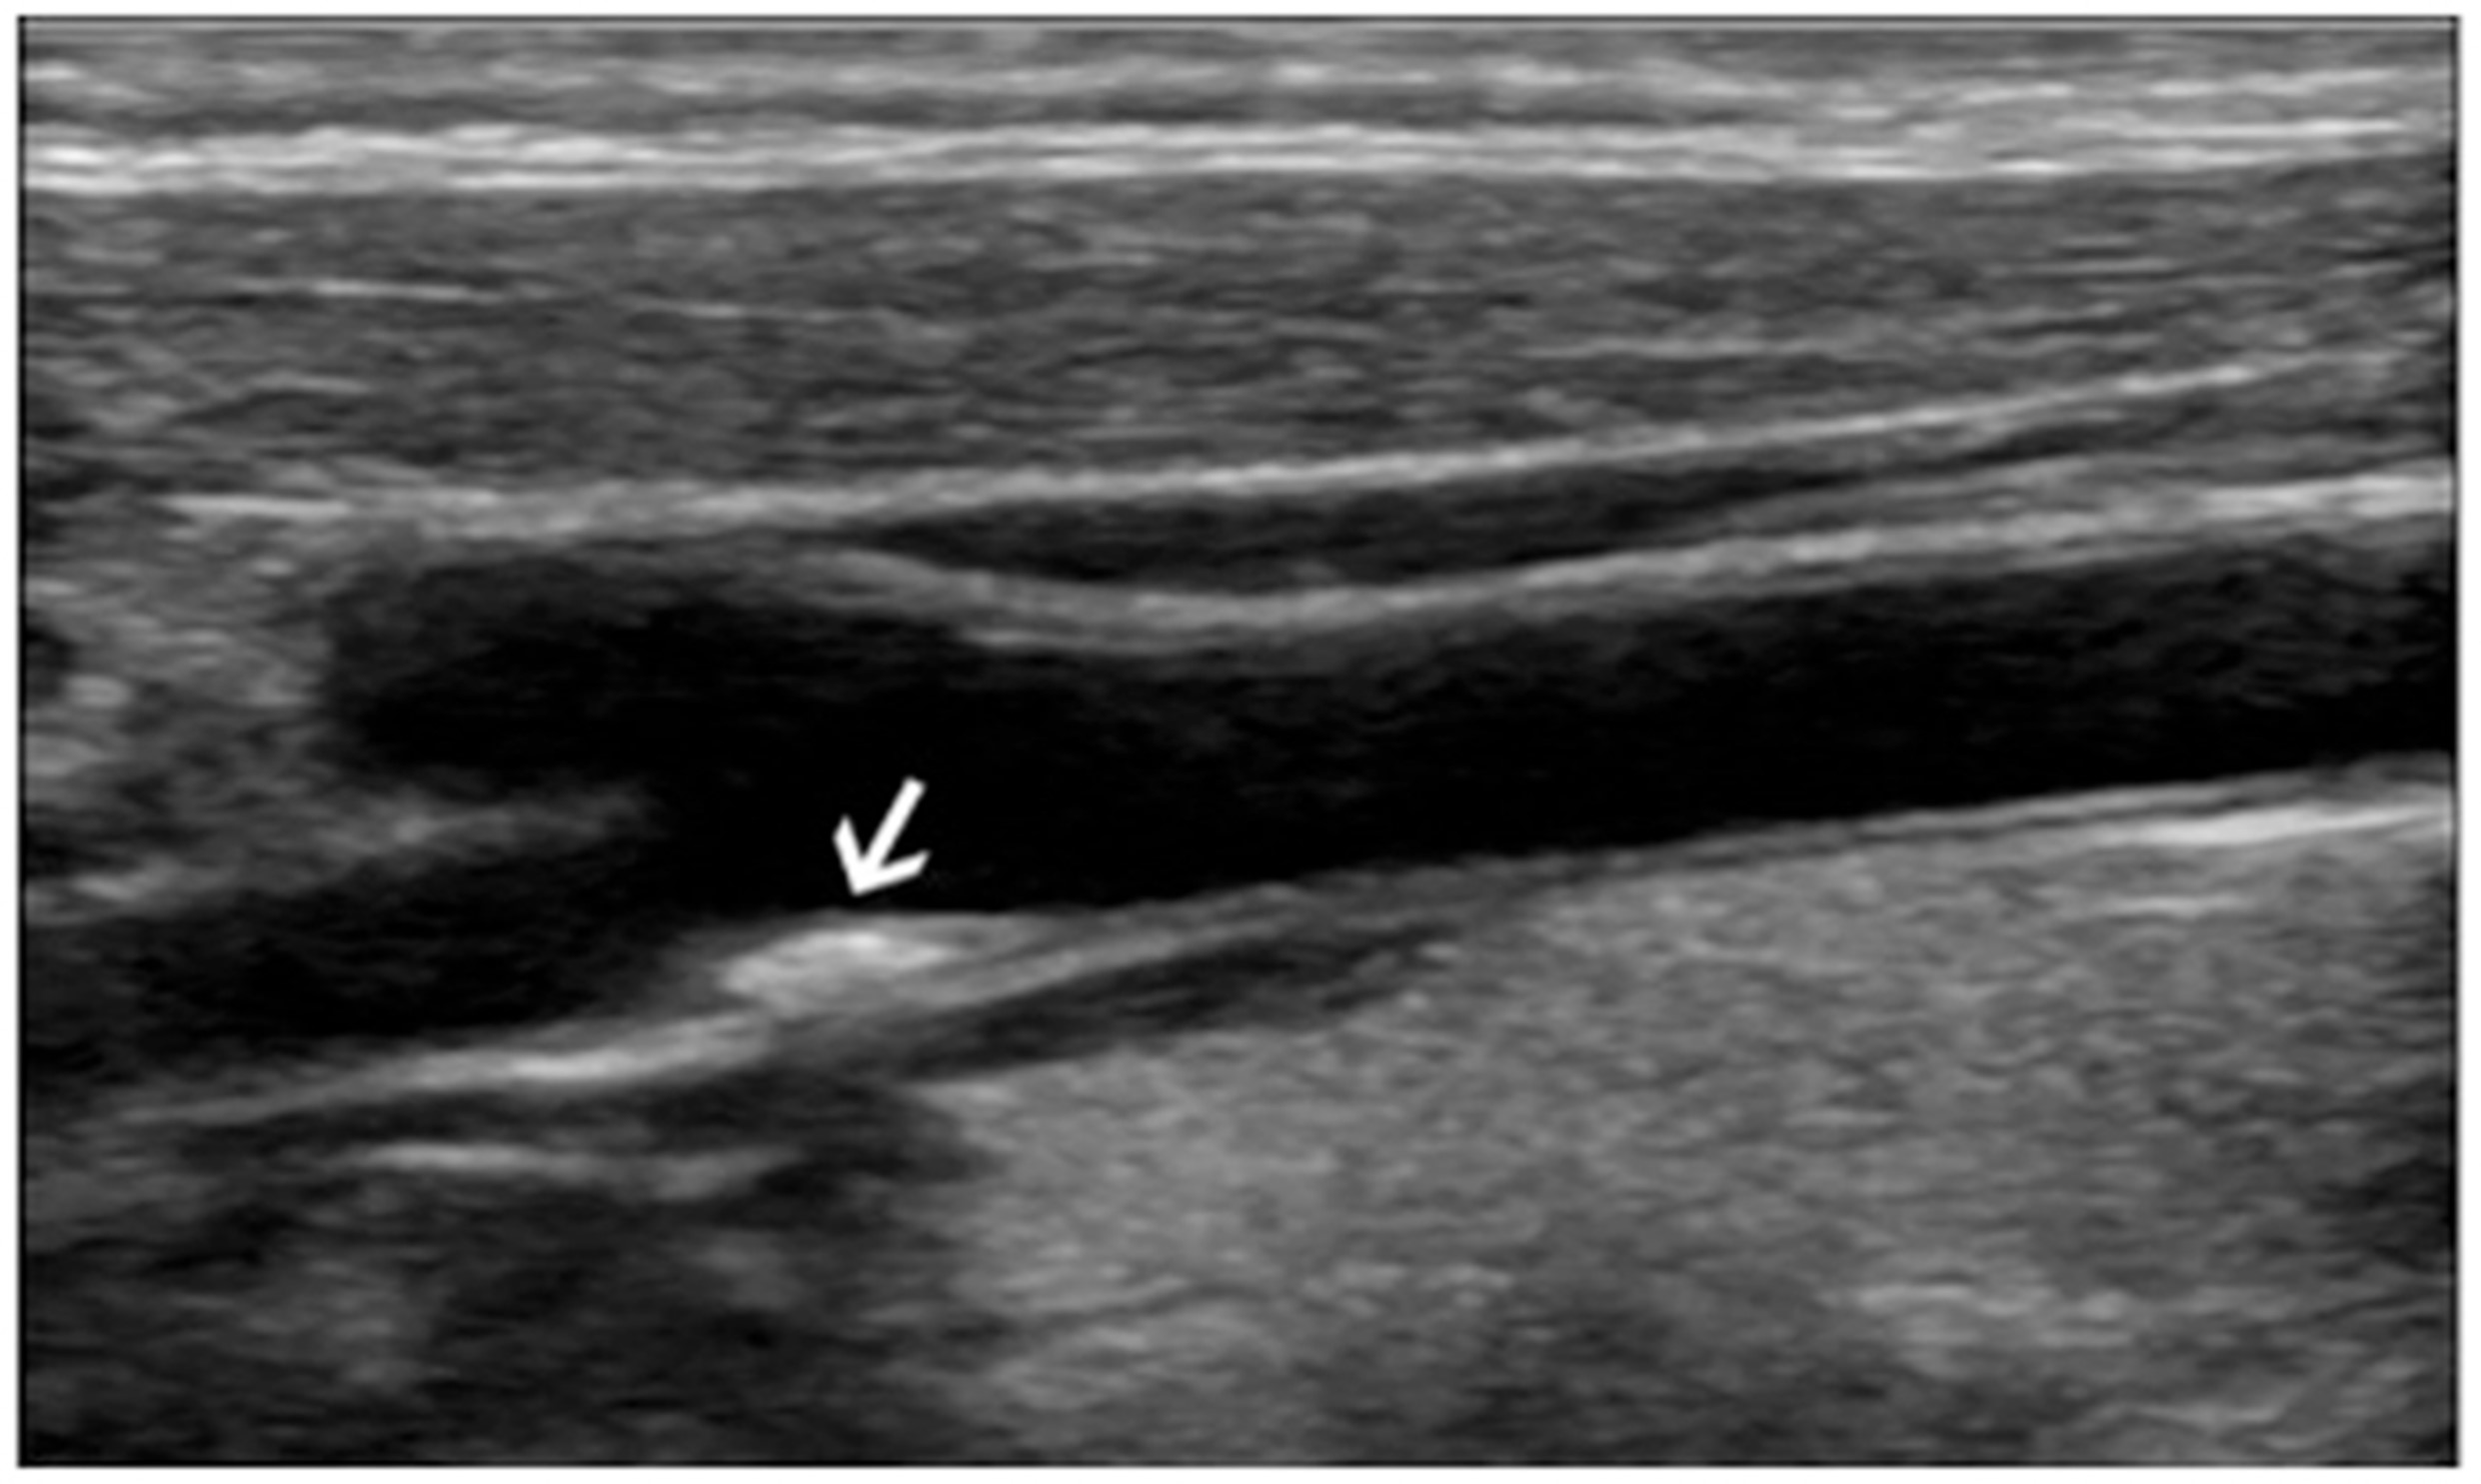

Hallazgos ecográficos

En la ecografía se evidencia placa de ateroma en bifurcación carotídea derecha con grosor de íntima-media de 0,8 mm.